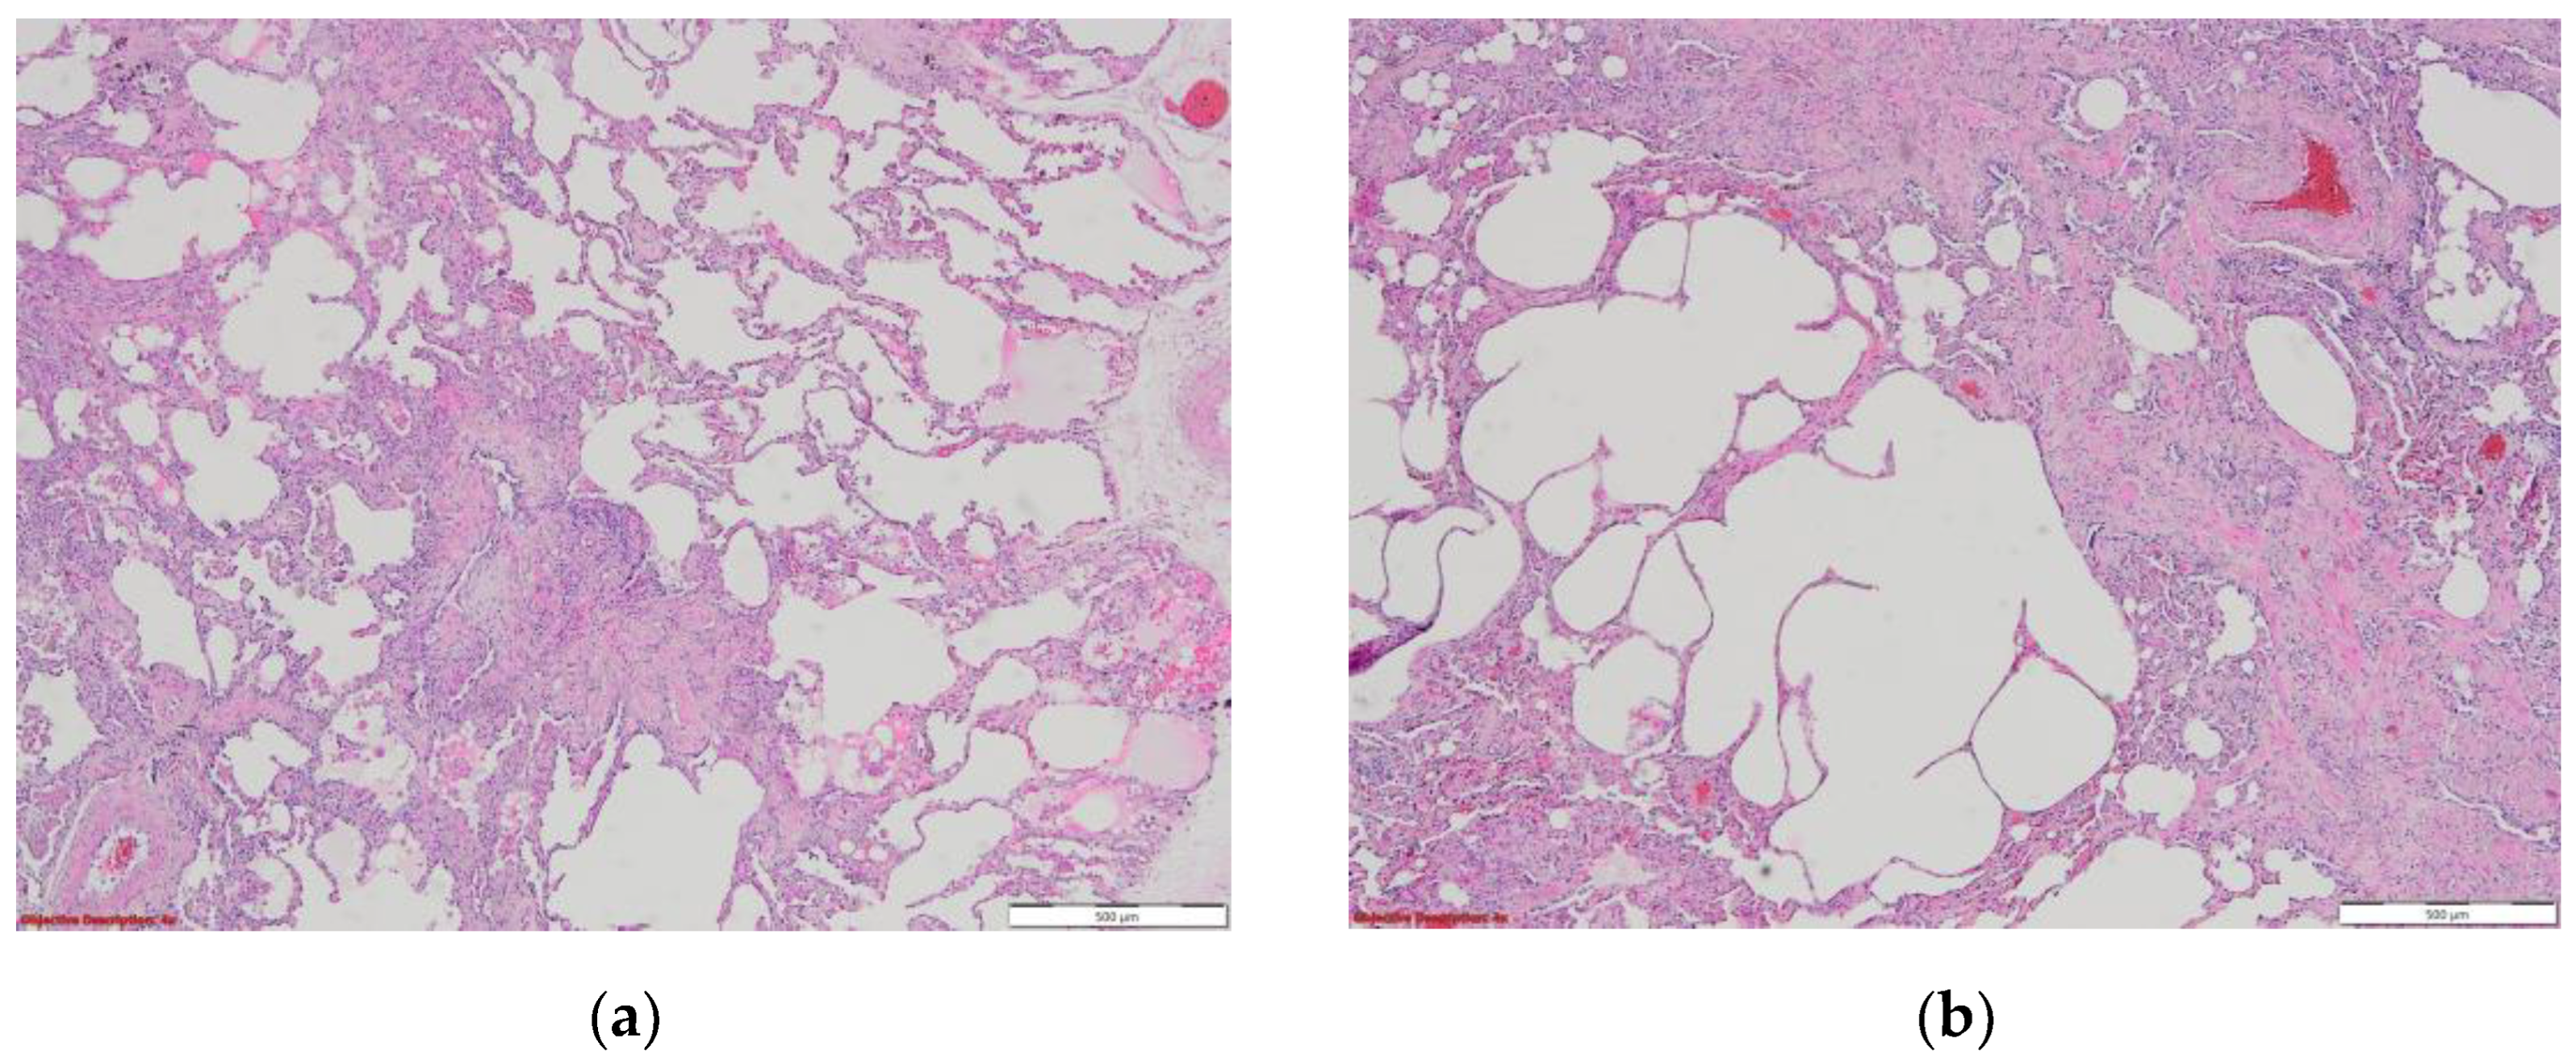

7. Histopathologic characterization

- Adachi, T.; Chong, J.-M.; Nakajima, N.; Sano, M.; Yamazaki, J.; Miyamoto, I.; Nishioka, H.; Akita, H.; Sato, Y.; Kataoka, M.; et al. Clinicopathologic and Immunohistochemical Findings from Autopsy of Patient with COVID-19, Japan. Emerg. Infect. Dis. 2020, 26, 2157–2161. [Google Scholar] [CrossRef]

- Deshmukh, V.; Motwani, R.; Kumar, A.; Kumari, C.; Raza, K. Histopathological observations in COVID-19: a systematic review. J. Clin. Pathol. 2020, 74, 76–83. [Google Scholar] [CrossRef]

- Martines, R.B.; Ritter, J.M.; Matkovic, E.; et al. COVID-19 pathology working group. Pathology and pathogenesis of SARS-CoV-2 associated with fatal coronavirus disease, United States. Emerg Infect Dis 2020, 26, 2005–2015. [Google Scholar]

- Tian, S.; Xiong, Y.; Liu, H.; et al. Pathological study of the 2019 novel coronavirus disease (COVID-19) through postmortem core biopsies. Mod Pathol 2020, 33, 1007–1014. [Google Scholar] [CrossRef]

- Li, Y.; Wu, J.; Wang, S.; Li, X.; Zhou, J.; Huang, B.; Luo, D.; Cao, Q.; Chen, Y.; Chen, S.; et al. Progression to fibrosing diffuse alveolar damage in a series of 30 minimally invasive autopsies with COVID-19 pneumonia in Wuhan, China. Histopathology 2020, 78, 542–555. [Google Scholar] [CrossRef]